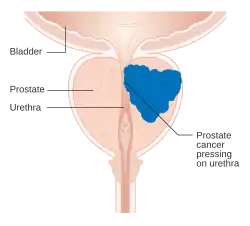

| Diagram of prostate tumor pressing on urethra | |

Prostate cancer is the uncontrolled growth of cells in the prostate, a gland in the male reproductive system below the bladder. Abnormal growth of the prostate tissue is usually detected through screening tests, typically blood tests that check for prostate-specific antigen (PSA) levels. Those with high levels of PSA in their blood are at increased risk for developing prostate cancer. Diagnosis requires a biopsy of the prostate. If cancer is present, the pathologist assigns a Gleason score; a higher score represents a more dangerous tumor. Medical imaging is performed to look for cancer that has spread outside the prostate. Based on the Gleason score, PSA levels, and imaging results, a cancer case is assigned a stage 1 to 4. A higher stage signifies a more advanced, more dangerous disease.

Early prostate cancer usually causes no symptoms. As the cancer advances, it may cause erectile dysfunction, blood in the urine or semen, or trouble urinating – commonly including frequent urination and slow or weak urine stream.[4] More than half of men over age 50 experience some form of urination problem,[5] typically due to issues other than prostate cancer such as benign prostatic hyperplasia (non-cancerous enlargement of the prostate).[4]